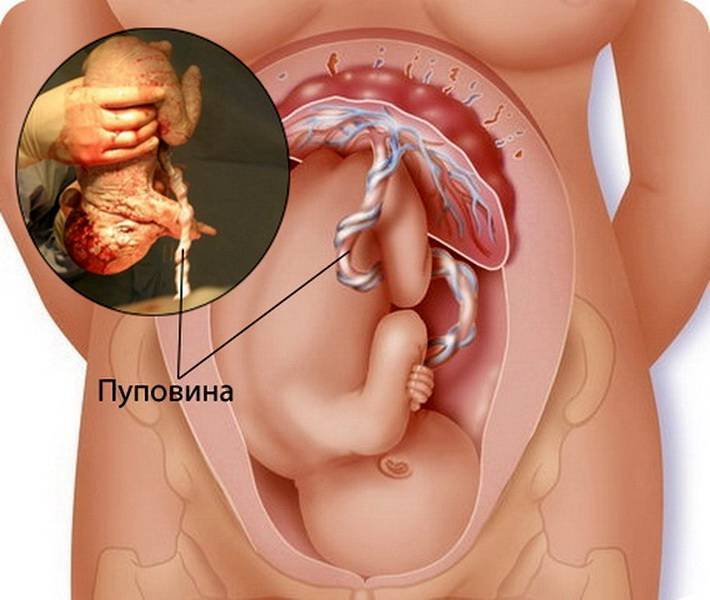

Околоплодный пузырь и плацента: структура и функции